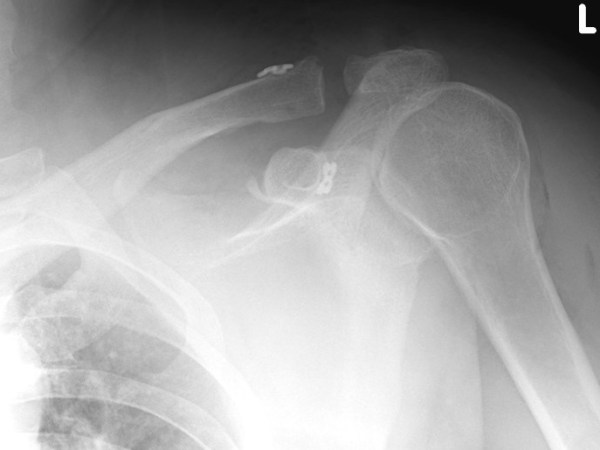

Première ligamentoplastie coraco claviculaire à l’hôpital Français d’Hanoï

Après un traumatisme direct sur le moignon de l’épaule , une lésion sévère de l’articulation acromio claviculaire peut nécessiter une prise en charge chirurgicale. Cette chirurgie peut se faire selon plusieurs modalités à « ciel ouvert » mais aussi sous arthroscopie, permettant des incisions plus petites et une récupération plus rapide . Nous avons choisi cette dernière technique, moderne, pour prendre en charge ce patient. Les douleurs après l’intervention étaient faibles et sa sortie a été autorisée le lendemain…